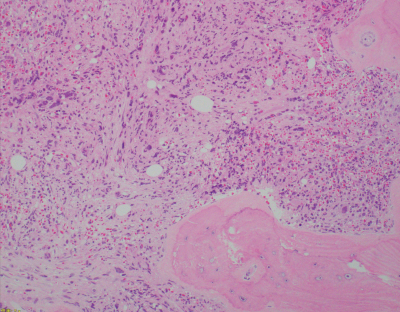

血液所見:赤血球243 万、Hb 7.8 g/dL、Ht 25 %、白血球 13,900(骨髄芽球 3 %、前骨髄球 3 %、骨髄球 6 %、後骨髄球 1 %、桿状好中球 3 %、分葉好中球 37 %、好酸球 14 %、好塩基球 13 %、単球 2 %、リンパ球 18 %)、血小板 8.0 万。末梢血好中球 BCR-ABL(FISH 法)陰性、骨髄穿刺は dry tap であった。骨髄の生検組織の H-E 染色標本と鍍銀染色標本を別に示す。